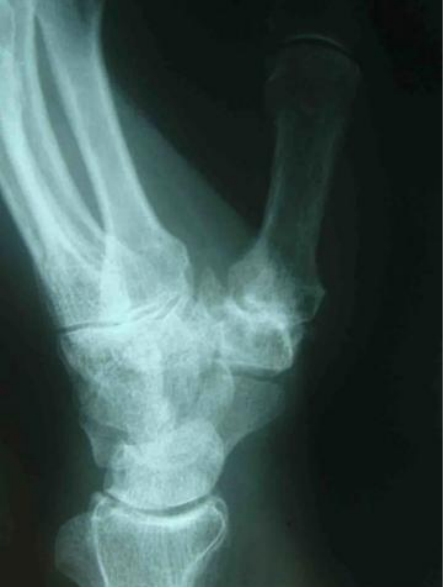

第一腕掌关节骨性关节炎X线影像学改变

X线表现:早期可无明显变化,随病情进展,出现典型的骨关节炎表现,关节间隙不对称性狭窄,软骨下骨硬化、囊性变,骨赘形成、骨端相对增大,以及第一腕掌关节的桡背侧半脱位。

第一腕掌关节骨性关节炎Ⅲ期影像学改变